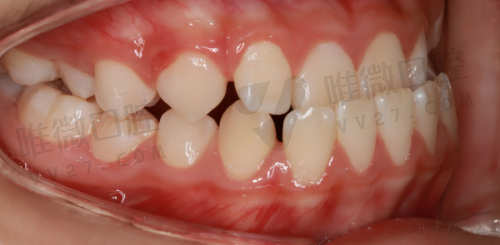

牙齿矫正收费情况

牙齿不整齐不仅影响美观,还可能影响口腔健康。襄阳瑞尔口腔门诊部的牙齿矫正价格根据矫正方式的不同而有所差异。传统金属矫正价格大概在 5000 - 10000 元;陶瓷半隐形矫正价格在 8000 - 15000 元;隐形矫正价格在 15000 - 30000 元左右。不同的矫正方式有不同的特点,大家可以根据自己的需求和经济情况选择。价格表如下: